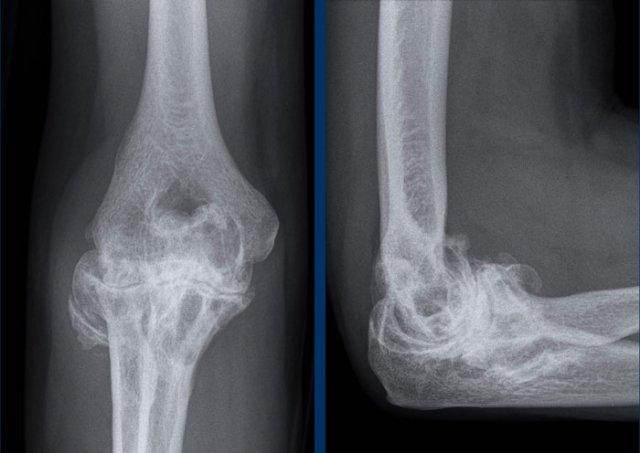

Nốt dạng thấp

Nốt dạng thấp là các cục cứng xuất hiện dưới da ở tới 20% bệnh nhân viêm khớp dạng thấp.

Các nốt này thường xuất hiện liền kề với các khớp bị lộ ra ngoài, dễ bị chấn thương hoặc chịu áp lực, chẳng hạn như các khớp ngón tay và khuỷu tay.

Trong thể bệnh này của viêm khớp dạng thấp, thường không có bất thường tại khớp.

Hình ảnh

Khối phần mềm (tức là nốt dạng thấp) trong lớp mô dưới da ở mặt lưng – bên ngoài của mỏm khuỷu.